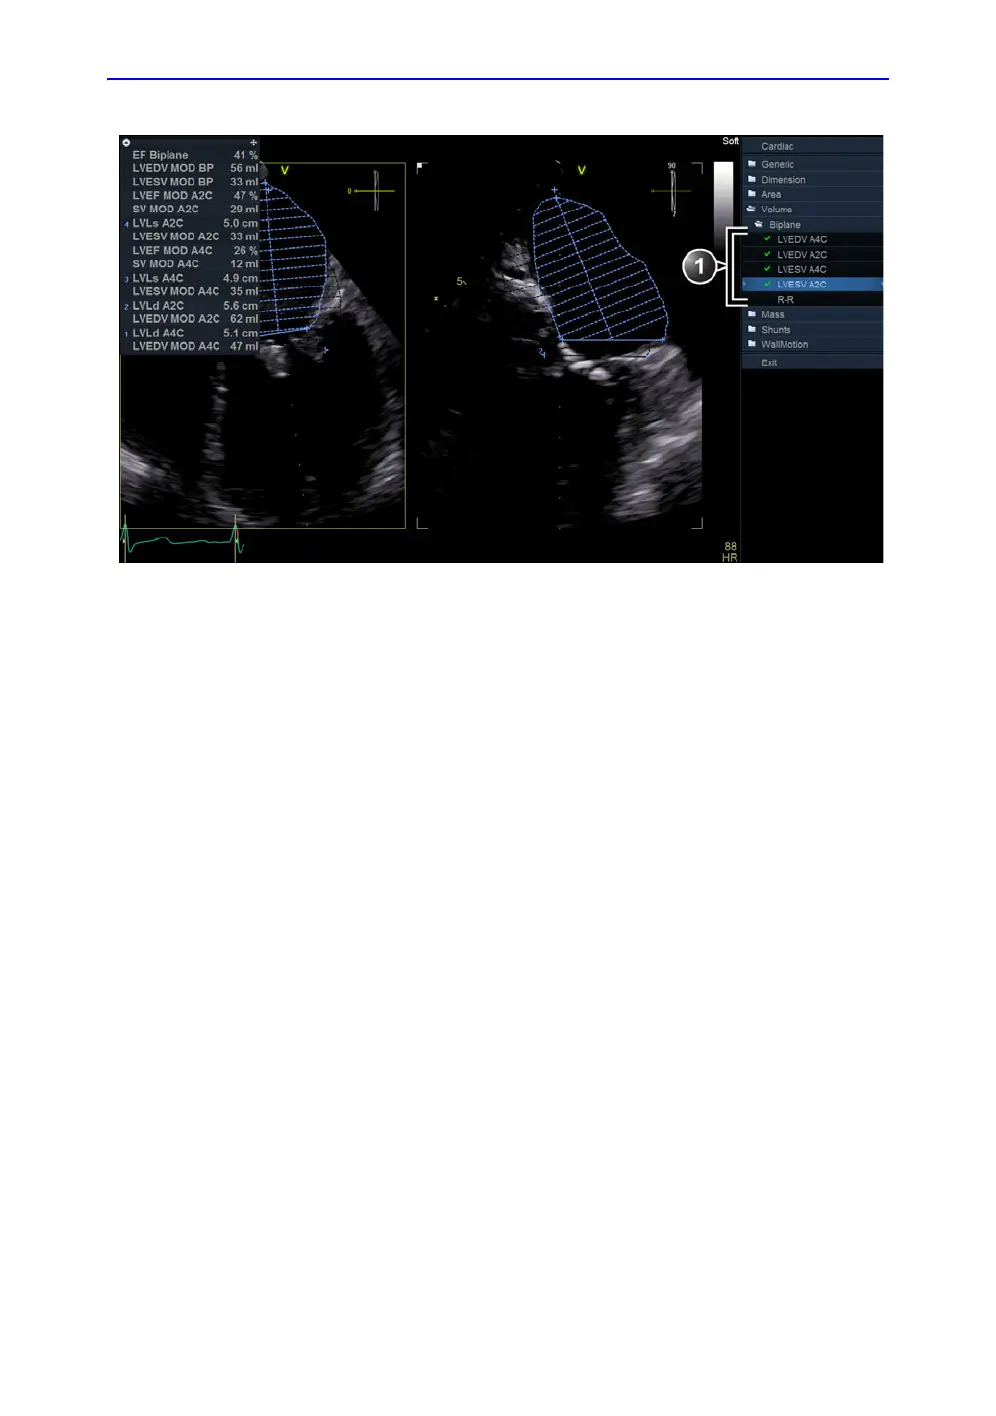

Figure 8-32. The Volume measurement screen (Bi-plane)

7. In scan plane 1 (yellow), place the cursor to the start point

for the trace.

8. Press Select and draw a contour of the left ventricle.

9. Move the cursor to the apex and press Select to measure

the length.

The trace tool for the Left ventricular end-diastolic volume

for the Apical 2 chamber view is selected.

10. Repeat steps 8 and 9 in the scan plane 2 (measurement in

the Apical 2 chamber view).

The trace tool for the Left ventricular end-systolic volume for

the Apical 4 chamber view is selected.

The Ejection fraction (Bi-plane) and the end-diastolic and

end-systolic left ventricular volumes are calculated.

1. Trace tools